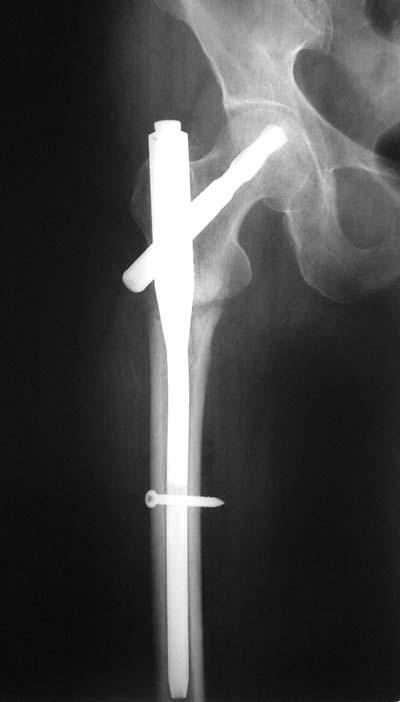

Стремишься? А что мешает вообще не использовать короткие штифты?

Не думаю так. см вложение.